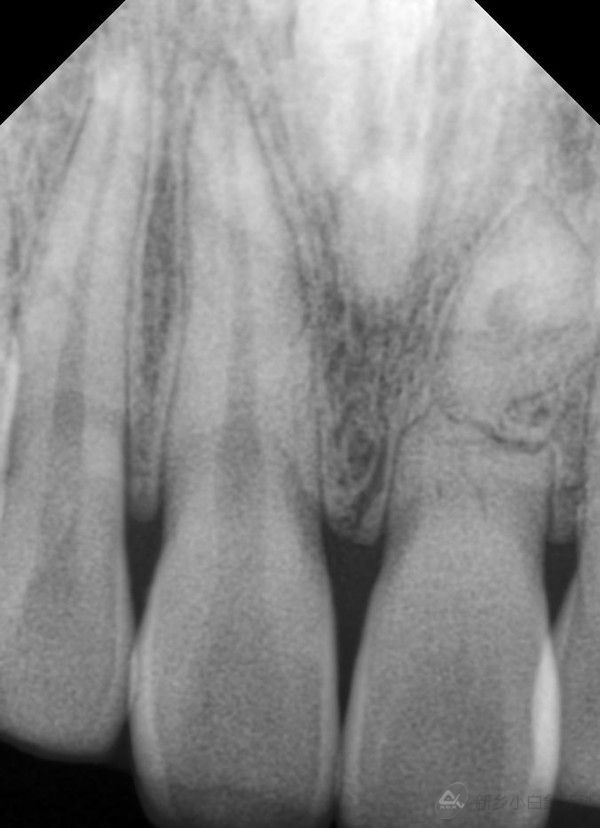

X片:21根中部见折断影;

1.jpg

治疗前